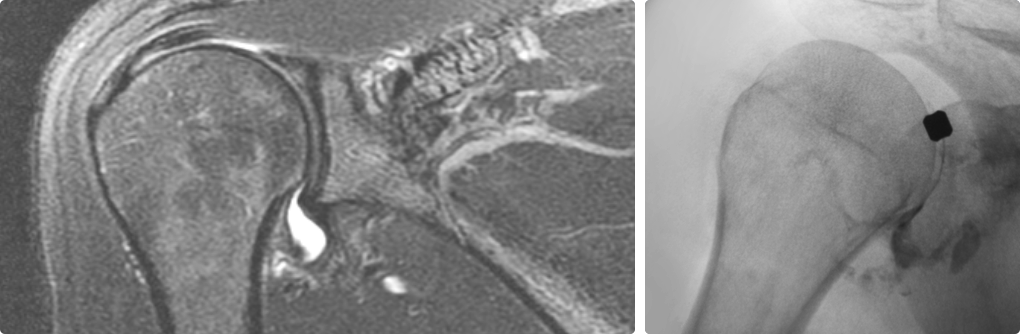

즉각적으로 통증을 완화해주고 어깨의 가동범위를 개선해주는 시술입니다.

주사 치료, 도수 치료 등을 하였으나 증상이 지속되는 경우

극심한 통증으로 스트레칭이 불가한 경우

정상 상태로 회복되는 걸리는 시간과 통증을 최소화 하고 싶은 경우